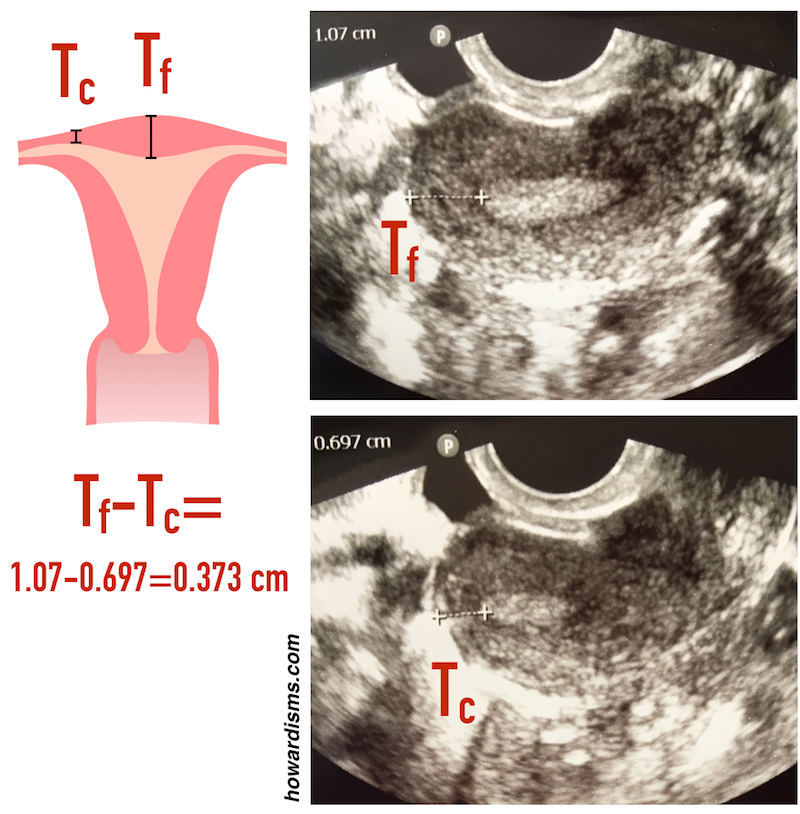

3. Low pressure or high?

There are two somewhat different goals of HSG: to test the patency of the fallopian tubes and to visualize the contours of the cavity. Higher pressure of the contrast medium helps distend the walls of the uterus but is also more likely to cause tubal or cornual spasm, leading to a false positive result. So, a low pressure technique is more effective if the primary aim is to test the patency of the tubes, which is the most common objective of HSG. Inject the contrast medium at a slow and steady pressure and you shouldn’t need more than 2 or maybe 3 ml for the whole study. If the patient reports significant cramping, you are probably using a too much pressure (and that cramping may be associated with tubal spasm).